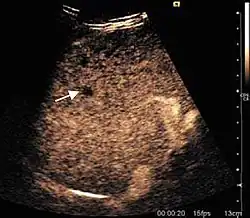

Liver abscess (2D and CEUS). 2D Examination reveals the fluid nature of the mass and imprecise delineation. CEUS examination shows congestion in the surrounding liver parenchyma and excludes a vascular tumor.

Liver abscess have heteromorphic ultrasound appearance, the most typical being that of a mass with irregular shapes, fringed, with fluid or semifluid content, with or without air inside. Doppler examination shows the lack of vessels within the lesion. CEUS exploration shows hyperenhancement during arterial phase close to the lesion, this being suggestive of a liver parenchymal hyperemia. During venous and sinusoidal phase the pattern is hypoechoic, and the central fluid is contrast enhanced. CEUS examination is useful because it confirms the clinical suspicion of abscess. In addition, it allows for an accurate measurement of the collection size and an indication regarding its topography inside the liver (lobe, segment).